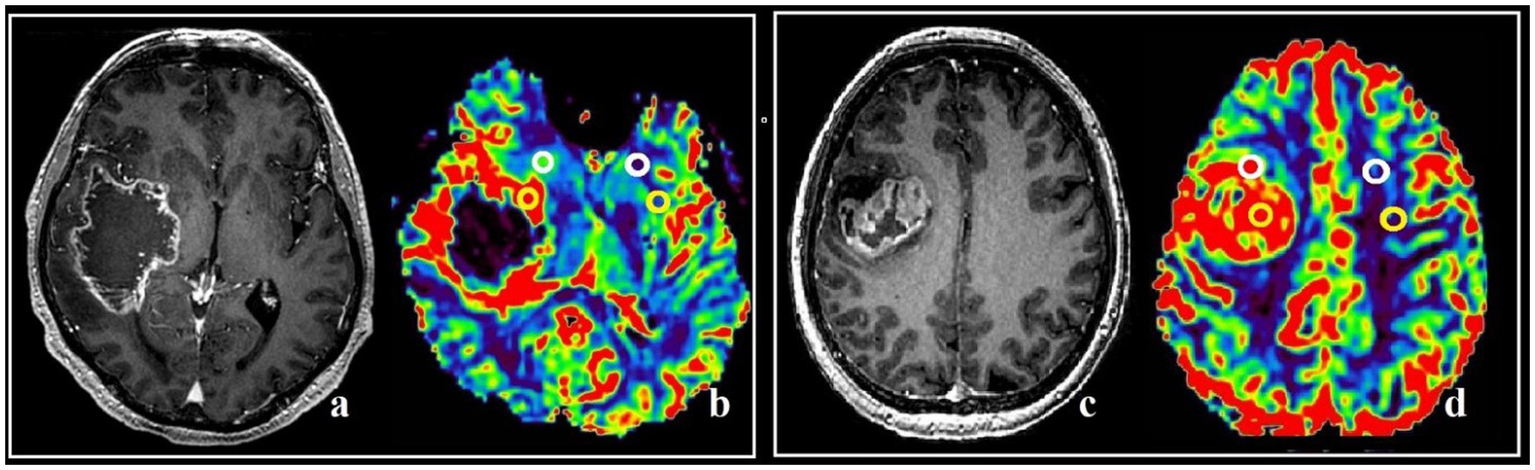

The maximum tumor blood flow was measured using colored perfusion maps to assess the areas of the tumor to be resected, as well as the postoperative assessment of the resection degree. In hyperperfused zones a region of interest (ROI) with the area of 20–30 m2 was placed. Next, the ROI with the highest values of mean tumor blood flow and volume (TBF, TBV) in the contrast-enhancing and the contrast-negative portions of the tumor was selected for analysis. To obtain the normalized values (nTBF and nTBV), blood flow and volume in the contralateral white matter were measured in the area located contra-laterally relative to the tumor using a ROI of the same area (Figure 1). In all cases there were no regions of altered MRI signal in the contralateral hemisphere.

Figure 1

Post-contrast T1 WI and MRI, and CT-perfusion of different patients (a–d). ROI segmentation with altered (yellow circles) and intact (white circles) BBB during comparison with post-contrast T1 series and DSC-T2* perfusion CBV map (a,b), and post-contrast T1 series with CT-perfusion CBV map (c,d). The parameters analysis was conducted both in affected and in specular contralateral hemisphere white matter.